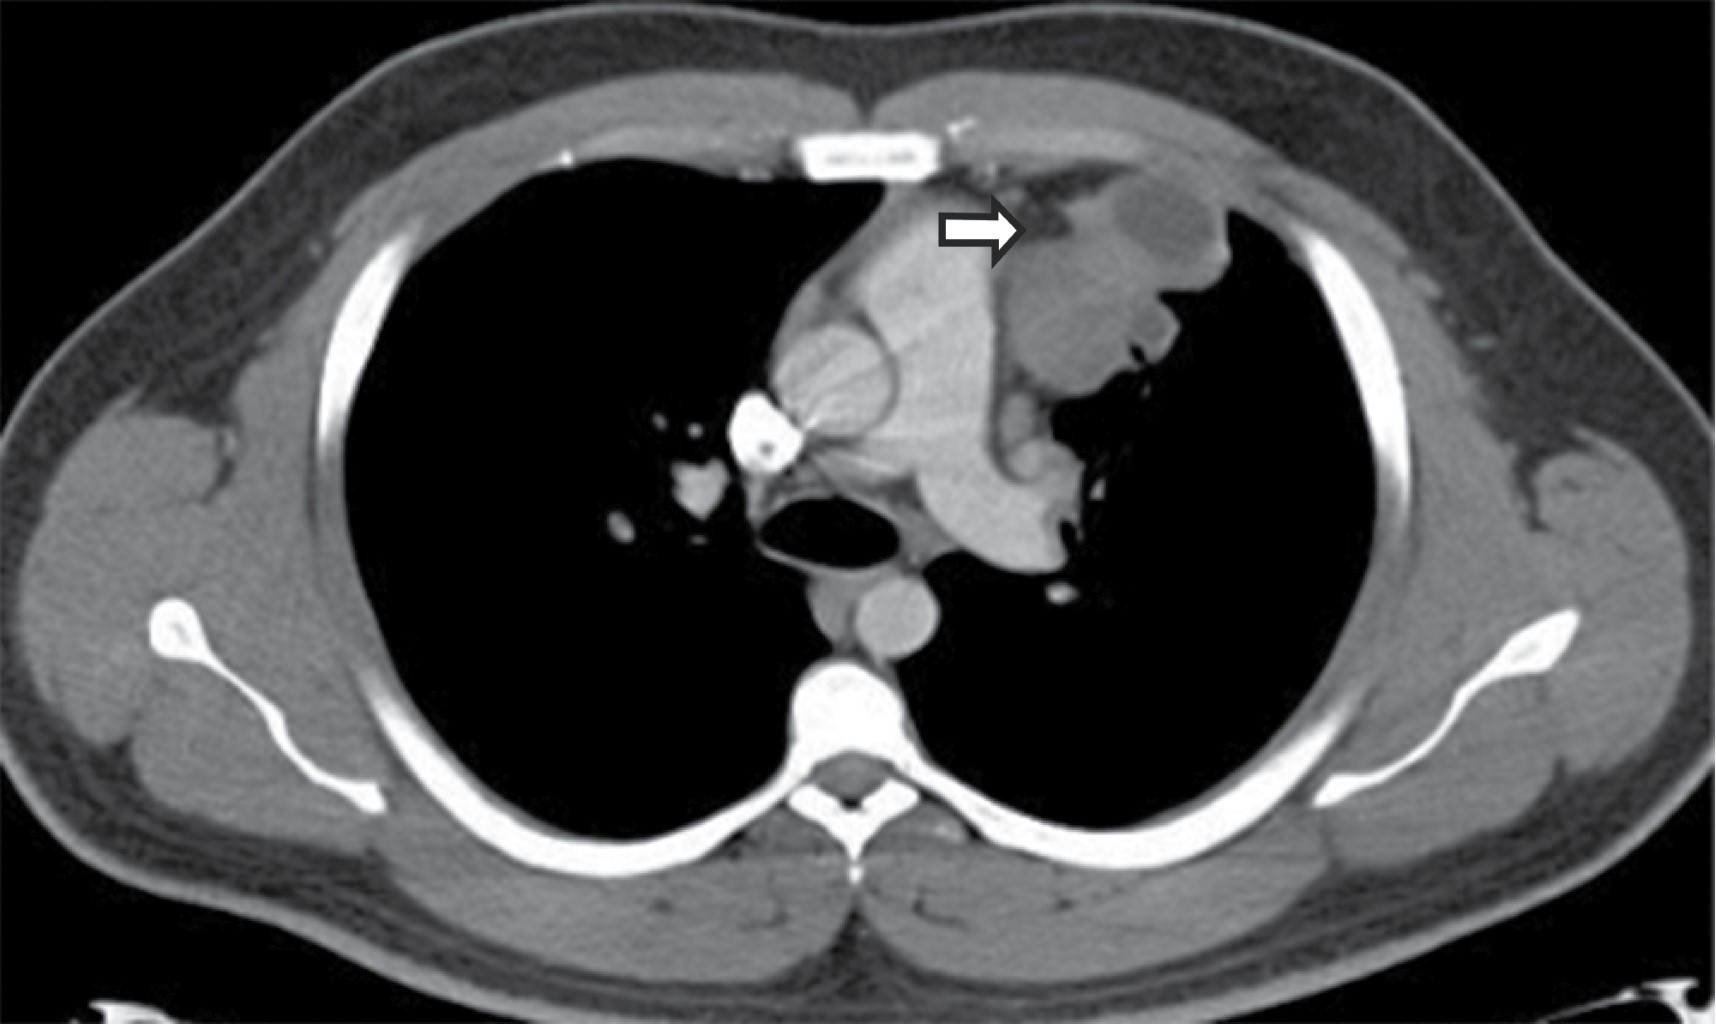

En la TC, típicamente se manifiesta como masas de atenuación de tejidos blandos que obliteran planos grasos mediastinales y encasilla o invade estructuras adyacentes. Sherrik y colaboradores8 identificaron dos patrones de invasión tomográfica: un patrón focal y un patrón difuso. El patrón focal (Figura 3) visto en 82% de los casos, se manifiesta como una masa con atenuación de tejidos blandos que con frecuencia calcifica (63%) y usualmente se localiza en las regiones paratraqueal derecha o subcarinal o en el hilio. El patrón difuso (Figura 4), visto en 18% de los casos como una masa infiltrante no calcificada que afecta múltiples compartimentos mediastinales. El patrón difuso ocurre en el estadio de otros desórdenes fibrosantes idiopáticos tales como fibrosis retroperitoneal.

El grado de realce es variable y es útil para describir encasillamiento u obstrucción de arterias pulmonares y venas. Reconstrucciones en dos o tres dimensiones pueden facilitar el abordaje quirúrgico o terapia local de estas lesiones.

La obstrucción venosa frecuentemente resulta en anormalidades parenquimatosa visible en la TC, tales como regiones focales o difusas de incremento de la atenuación parenquimatosa focal o difusa, atenuación en vidrio deslustrado, y engrosamiento septal interlobular.